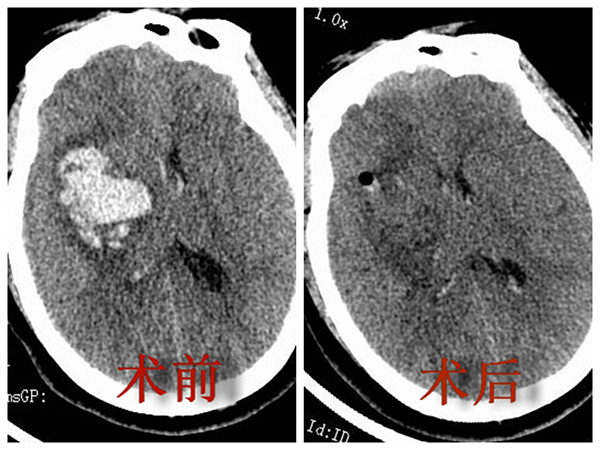

12月28日,家住凤阳县60岁的叶女士突发意识不清,经当地医院对症予止血、脱水、降颅压等保守治疗治疗,但病情愈发加重,紧急转送二附院神经外科。经颅脑CT明确诊断为高血压脑出血,出血量40ml。神经外科副主任王大巍博士立即组织病案讨论、制定治疗方案。专家组根据出血形状,出血量,患者的意识状态和患者的身体条件,认为患者符合行微创神经内镜下脑内血肿清除手术。随即,王大巍博士在其团队密切配合下,借助神经内镜的照明系统和显示系统,应用常规显微神经外科手术器械,通过直径3cm小骨窗切口彻底完成脑内血肿清除术,次日病人复查CT脑内干净无血肿,意识清醒。8小时后复查CT,显示内血肿清除干净,无明显残留及再次出血。